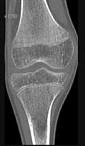

男,46岁,膝关节疼痛,结合图像,最可能的诊断是()A.骨质硬化B.骨质疏松C.骨质软化D.骨髓瘤E.转移瘤

问题 男,46岁,膝关节疼痛,结合图像,最可能的诊断是()

选项 A.骨质硬化 B.骨质疏松 C.骨质软化 D.骨髓瘤 E.转移瘤

答案 B